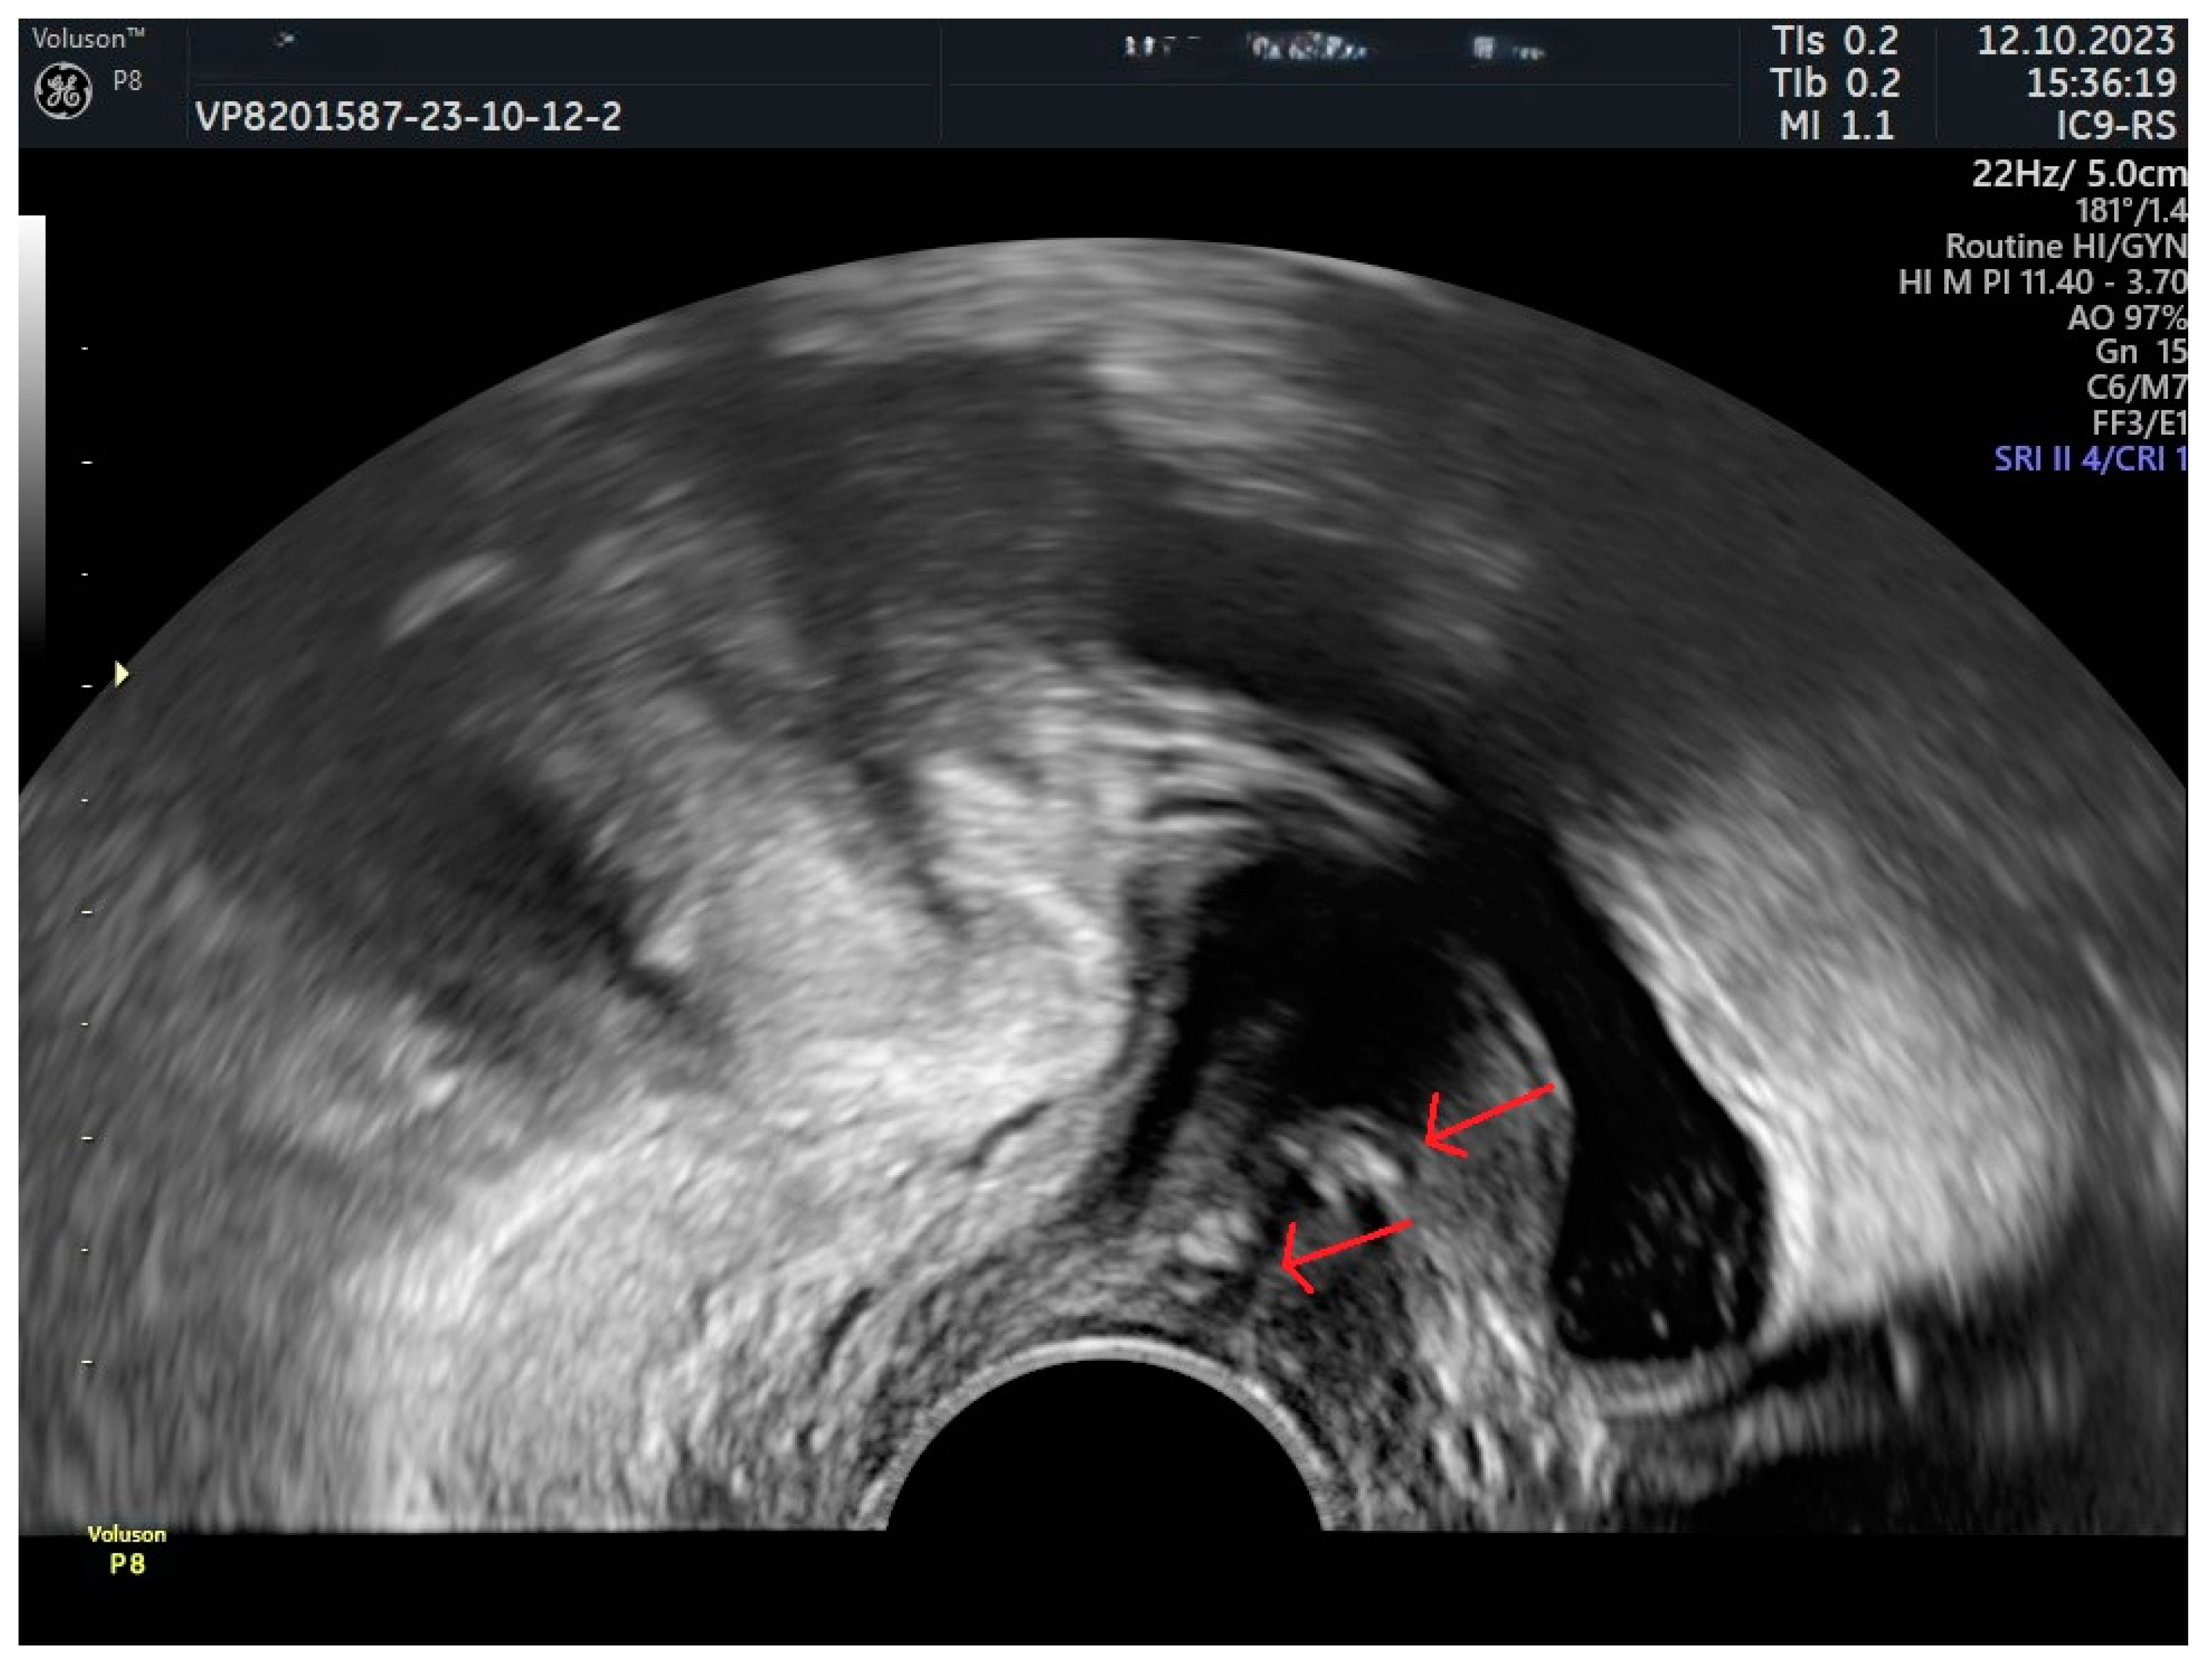

| Sling erosion | Lou et al., 2023 [87] | A case of sling erosion into the bladder with formation of secondary bladder stones. |

| Viragh et al., 2018 [88] | US could detect erosions not visible in cystourethroscopy. | |